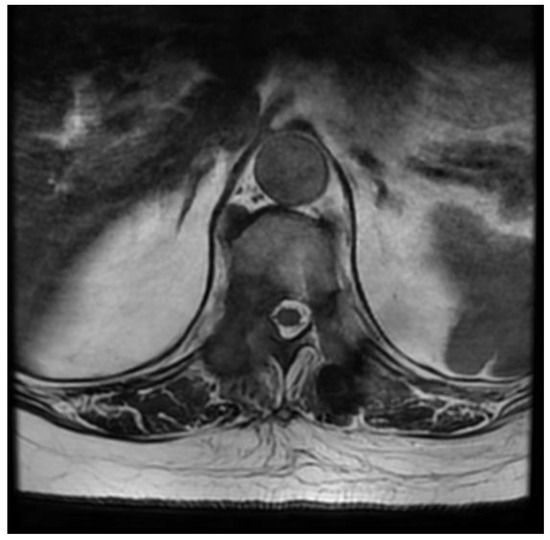

Fully Endoscopic Spine Separation Surgery in Metastatic Disease—Case Series, Technical Notes, and Preliminary Findings

2. Materials and Methods

3. Results